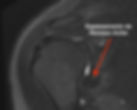

O diagnóstico da capsulite adesiva é feito clinicamente através do exame físico e história pregressa. Exames adicionais são importantes para descartar diagnósticos diferenciais, porém não são essenciais. A Ressonância Magnética, por exemplo, pode não apresentar nenhuma alteração dependendo da fase da doença. Na fase de rigidez pode apresentar espessamento de ligamentos e do recesso axilar.